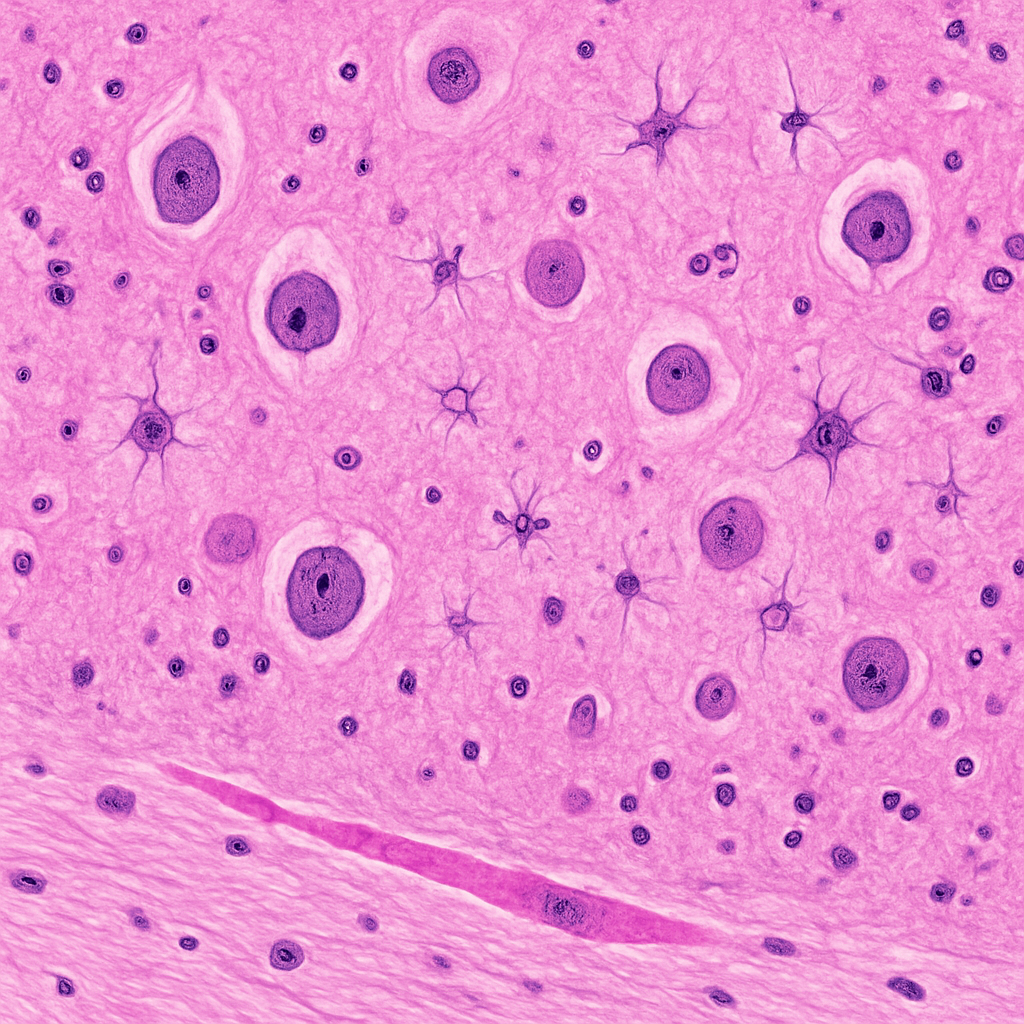

Centrifuged urine sediment showing casts, crystals, and cells